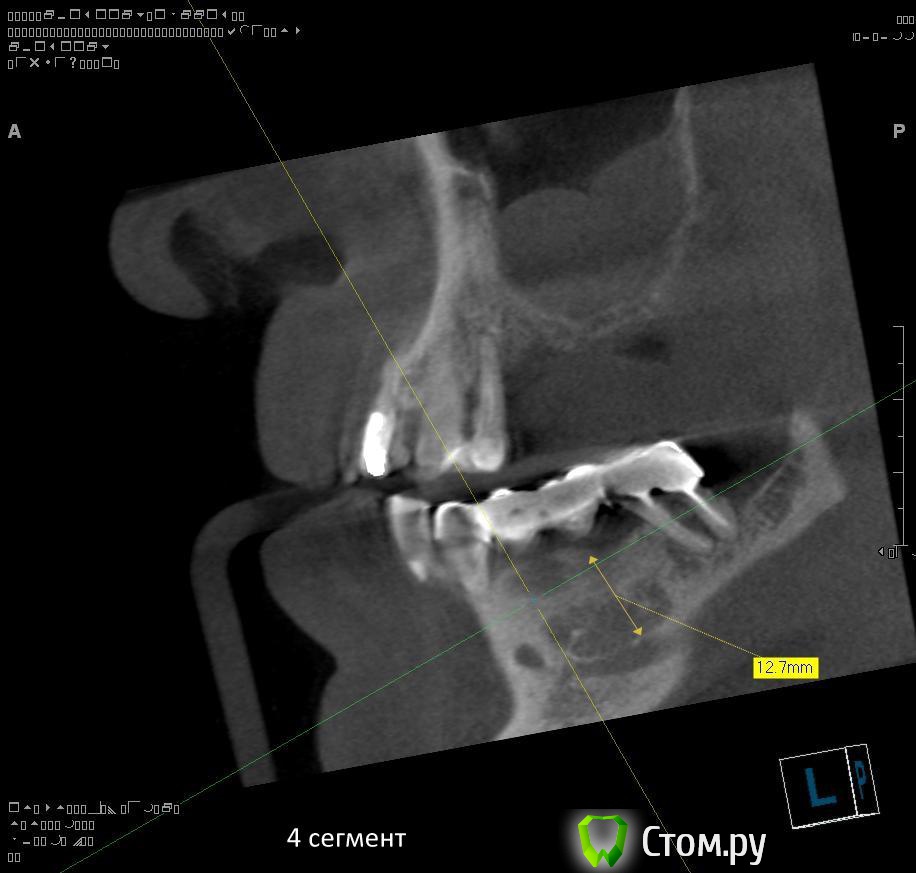

4. через 1,5 - 2 месяца после удаления 4.4 и 4.7 провести установку имплантатов в 4 сегменте?

5. в какие позиции должны быть поставлены имплантаты в 4 сегменте сбоку (4.5, 4.7?)?